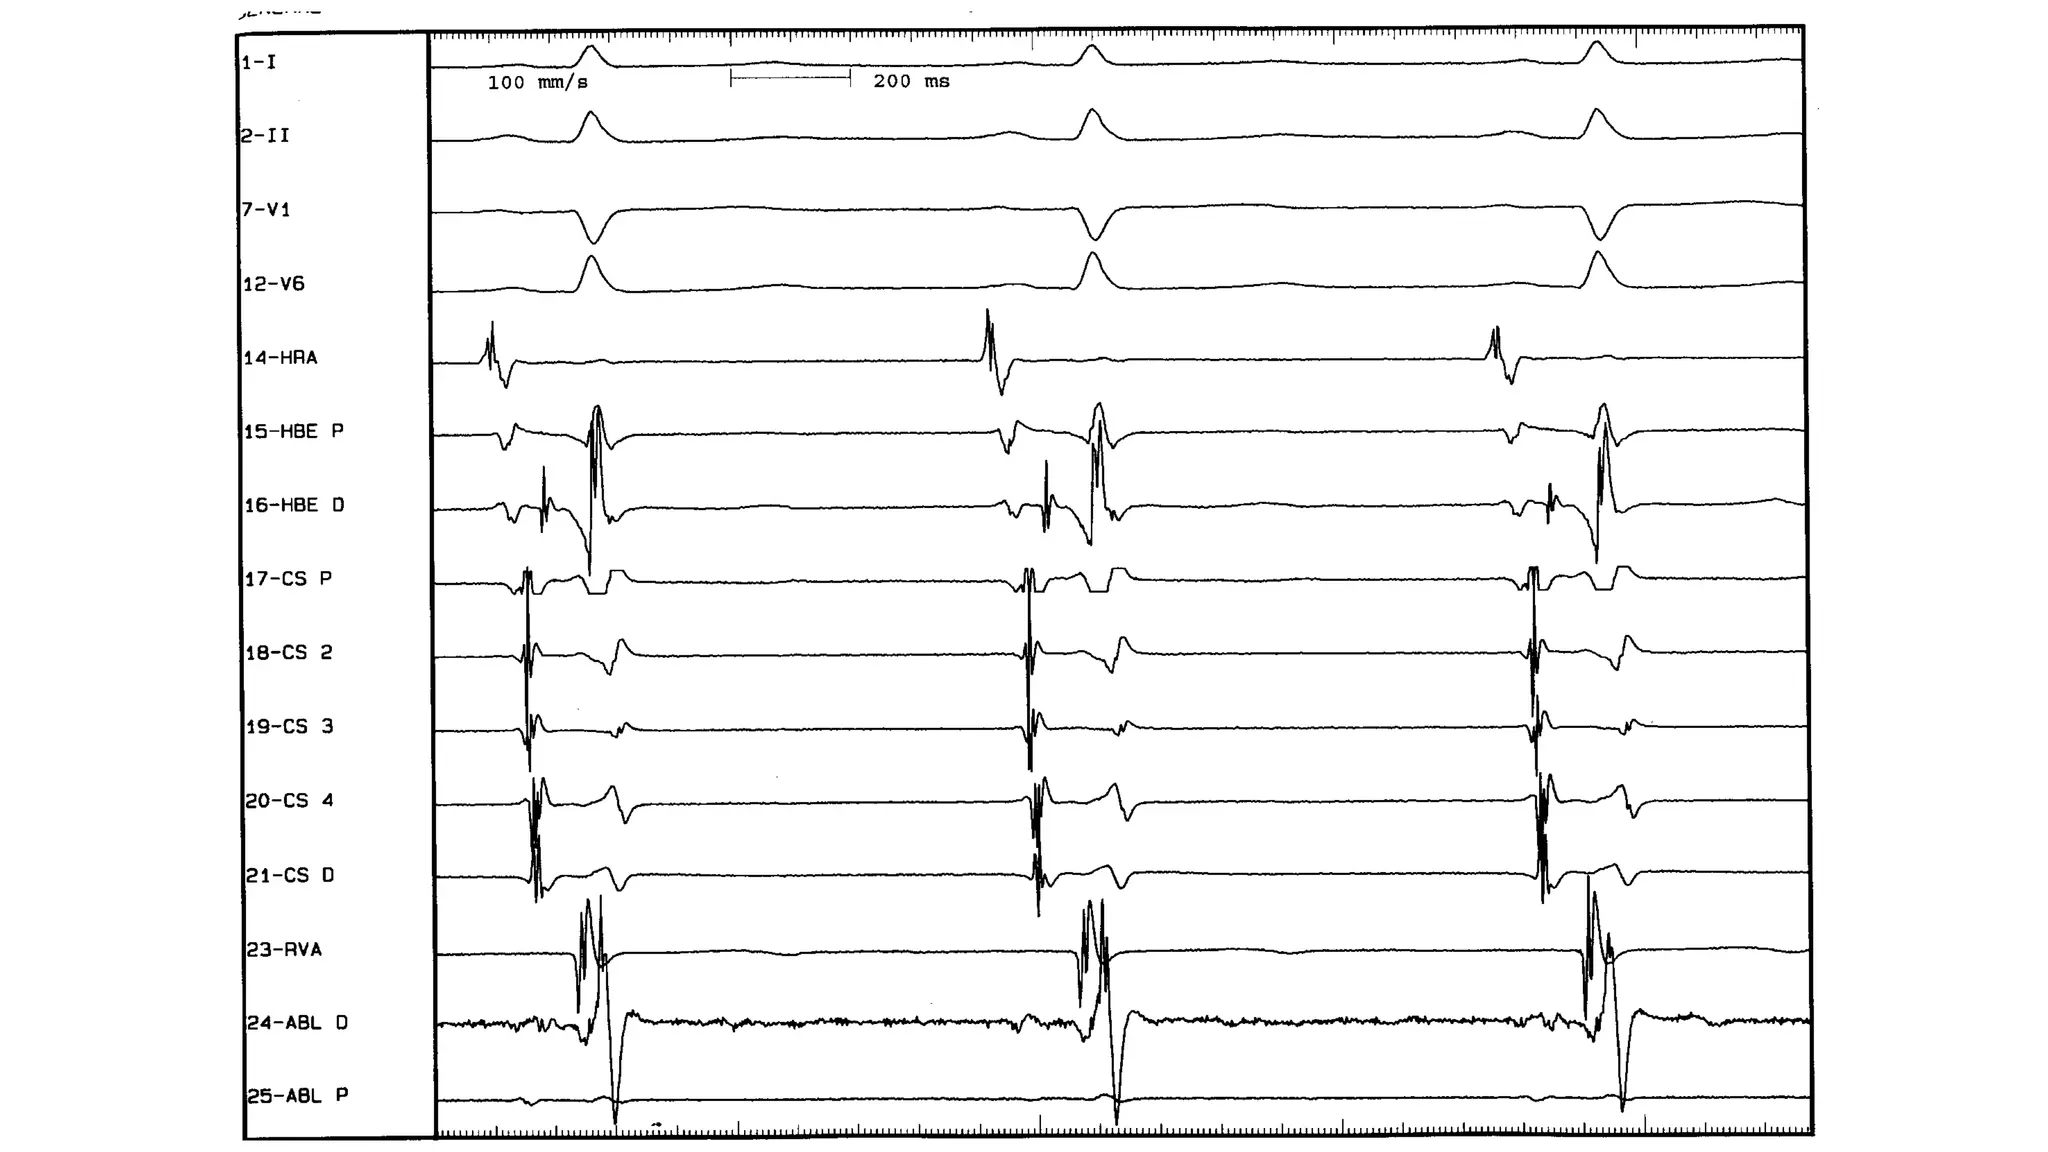

An electrophysiologic study involves inserting electrode catheters into the heart to record electrical activity and induce arrhythmias. The document discusses: 1. The procedure involves placing catheters in the heart to record electrograms from the atria, His bundle, ventricles and coronary sinus. 2. The aims are diagnostic to evaluate arrhythmias and bradycardias, and therapeutic for ablation of arrhythmias. 3. Key measurements taken include intervals between P waves, His bundle activation and QRS complex to identify conduction abnormalities. 4. Tracings are analyzed to determine the rhythm, sequence of activation, effects of pacing, and identify arrhythmia mechanisms like accessory pathways